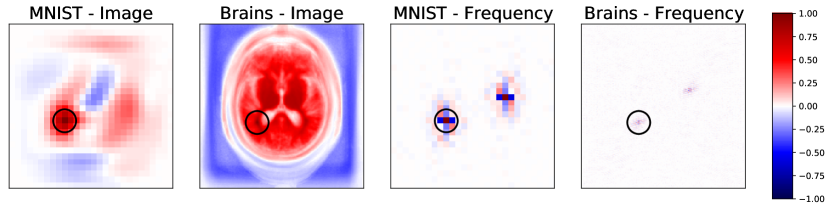

Recently, neural networks have emerged as an alternative approach for MRI reconstruction (Aggarwal et al., 2018; Hammernik et al., 2018; Hyun et al., 2018; Lee et al., 2017; Putzky and Welling, 2019; Quan et al., 2018; Schlemper et al., 2017; Sun et al., 2016; Yang et al., 2017; Aggarwal et al., 2018; Hammernik et al., 2018; Cheng et al., 2018; Han et al., 2019; Zhu et al., 2018; Duffy et al., 2021; Haskell et al., 2019; Johnson and Drangova, 2019; Küstner et al., 2019; Pawar et al., 2018; Shaw et al., 2020; Oksuz et al., 2019; Usman et al., 2020; Benou et al., 2017; Jiang et al., 2018; Manjón and Coupe, 2018). Most existing architectures are based on purely frequency space representations or purely image space representations. Here, we propose and demonstrate joint frequency-image space representations that enable networks to learn a wide set of tasks including and beyond the extensively studied undersampled reconstruction. To motivate our approach, we examine the correlation structure for frequency and image space representations in Fig. 1. Local neighborhoods around a pixel exhibit strong correlations, suggesting that local convolution operations, which are widely successful on image space computer vision tasks, might also be useful when applied to frequency space data to capture this local structure. Convolutional operations in frequency space promise to enable direct correction of local frequency space artifacts corresponding to global image space effects, while convolutional image space processing facilitates complementary correction of artifacts that are best captured in the image domain.